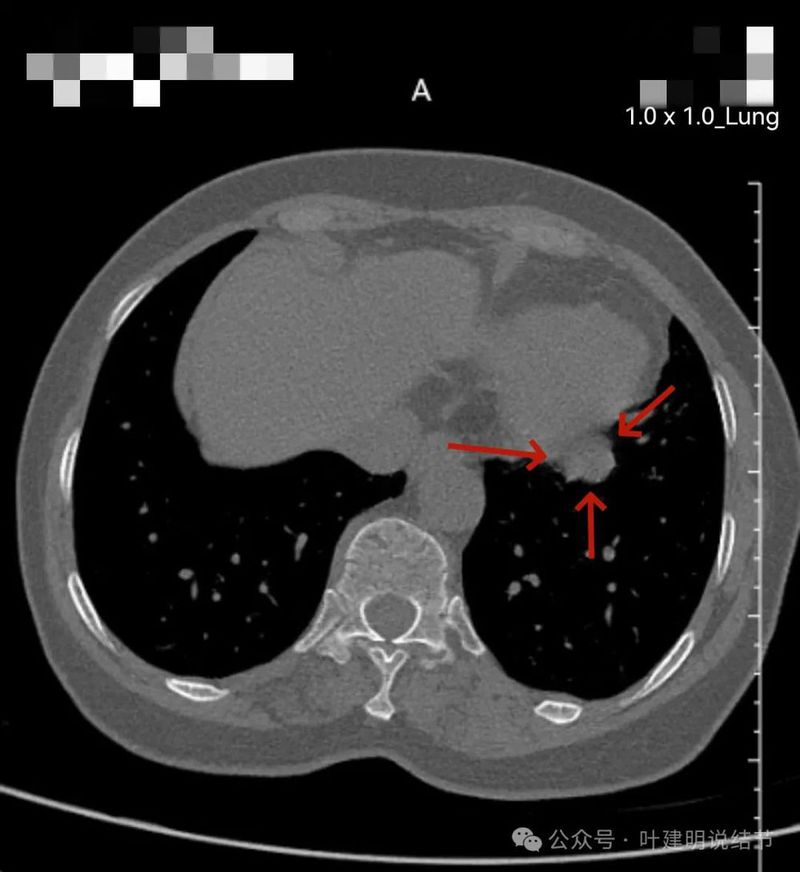

左下实性结节,明显有膨胀感,边缘虽然光滑,但给人感觉不舒服,恶性的可能性大些。

纵隔窗见病灶实性密度,与膈肌间有低密度线状间隙。

两肺多发小结节,大部分是实性微小的,没有临床意义,只需随访;部分是淡而小的磨玻璃结节,也意义不大,能常规年度随访。主病灶则在左下叶近膈面处,此灶实性,有膨胀感,表面有浅分叶,但邻近膈肌与胸膜,未见明显胸膜牵拉,说明收缩力不明显。总体轮廓较清,没有卫星病灶,也无周围炎性渗出性或磨玻璃成分。此灶定要说良性或恶性,仍不能定。符合良性的是:边缘较为光滑,缺乏收缩力,未见血管征;符合恶性的是:有膨胀性与浅分叶,周围清晰不似普通炎性。但我们若换个角度来看问题:此灶若确实是恶性,那是实性的肺癌,随访是有风险的;若确实是良性,若予以单孔胸腔镜下局部楔形切除对肺功能影响并不大,手术风险也低,既能明确诊断又去除了病灶。也就是说:事实上恶性再随访存在风险,而事实上良性切了影响不大,手术的利弊权衡是利大于弊的(当然若确实是恶性,又做了手术,当然更是应该的)。所以我的意见:倾向恶性点,建议微创手术。如果对手术比较抗拒,也可适当口服抗炎治疗10-12天,之后间隔6-8周复查下增强CT或PET-CT(PET更有价值点)再决定也是可行的。意见供参考!

两的囊腔灶目前不太确定,磨玻璃灶轮廓清楚边界清,多是肿瘤范畴的可能性大,但除了右侧混合密度那处以外,其他的风险低能随访。关键是主病灶在左下叶这处,这才是目前要重点考虑的。如果此处是恶性而且恶性程度较高,那么其他那些根本不需要管,因为决定预后以及是否中期或晚期的关键是左下主灶。从膨胀性、浅分叶、胸膜间隙征等许多特征来看,我是考虑大概率是恶性的,而且两肺微小的会不会可能是此灶的转移也难说。但毕竟是首次发现,时间还短,谨慎抗炎后短期随访,几周或1-2个月左右的时间也不至于影响预后,真如果恶性程度很高,也不是急在几周内的事。但短时间随访无好转(这种可能性大得多),还是要及时取得病理依据的。从实用与马上明确并指导后续治疗来讲,我是非常倾向直接行胸腔镜下探查及左下叶部分切除,术中送快速切片来明确的。当然如果术前查下PET更好,主要是想看两肺微小的结节是不是有高代谢,考虑不考虑转移。只是微小结节其实也很难反应出代谢是否增高,有时做了PET也无法确定。我总认为,临床医生的决策应该:直接、高效、权衡!